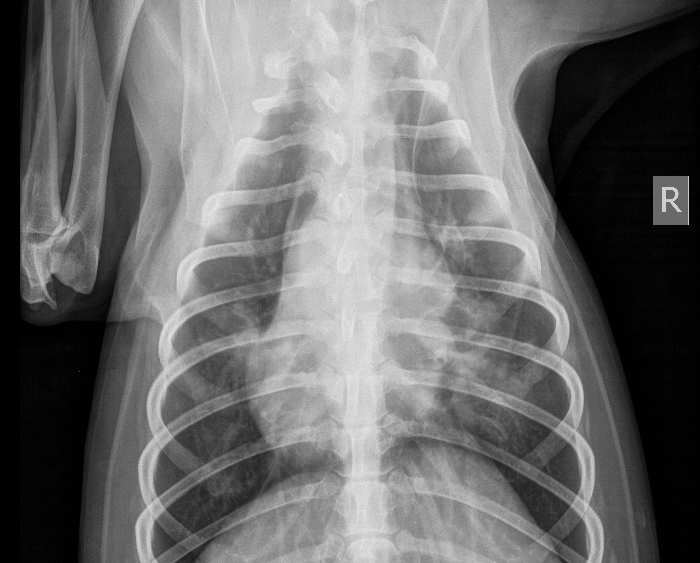

RTG šalje slike i nalaz ambulanti, ambulanta čita nalaz. Dakle ako želite razgovarati s doktorom o slikama, onda je to doktor na RTG-u, a ne u ambulanti. To je dobro, jer se na slikama mogu uočiti i druge promjene, pa ćete odmah dobiti informaciju o tome iz prve ruke.

Tražite drugo mišljenje kada dobijete nalaze, ako nije 100% sigurno što se vidi, nemate što izgubiti, a ne želite biti onaj slučaj kada nisu dobro interpretirali ili vidjeli što se događa sa psom, pa su liječili krivu stvar, a pas je u međuvremenu uginuo od prave stvari.

Slike su sada u elektronskom obliku, te iste ne dobivate automatski. Na zahtjev dobijete sprženi CD i aplikaciju koja otvara iste slike tako da ih možete otvoriti na osobnom računalu i isprinati prema potrebi.